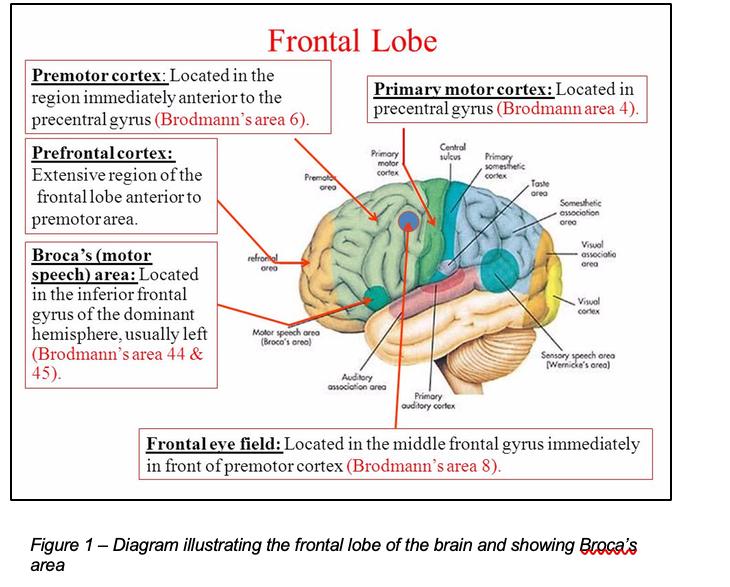

Mr. D.C. is a 75-year old gentleman brought to casualty after a neighbour found him unable to speak. Since he was severely aphasic, he was unable to give a proper history. The patient was able to understand commands, making this a pure expressive aphasia. He was also noted to have right hemiparesis and right facial weakness. On examination, Mr D.C. was found to have 0/5 power on the right half of his body and 3/5 power on the left side of his body using the MRC muscle power assessment scale. He was noted to have right facial weakness in an upper motor neurone lesion pattern. He was urgently admitted to a medical ward and a CT scan was requested. The scan confirmed a left middle cerebral artery (MCA) ischaemic infarct affecting the basal ganglia and Broca’s Area in the inferior frontal lobe. Fact file on Expressive Aphasia Expressive aphasia, also known as Broca’s aphasia or non-fluent aphasia, is a condition which is characterized by a loss of the ability to produce both spoken and written language. Although patients are unable to communicate properly, their understanding of speech is mostly intact and much better than when compared to their speech. The most common cause of Broca’s aphasia is a left middle cerebral artery thrombus or embolus causing a stroke which affects the third frontal convolution of the frontal lobe, which is also known as Broca’s area (Figure 1), and extending into the white matter. However, it may also be caused by any disease or injury which might affect Broca’s area. The fact that the area of this lesion is anterior to the inferior part of the precentral gyrus, which is responsible for executing voluntary motor movements, explains why there is also associated weakness in the right upper extremity in this condition (“Stroke Rehabilitation: A Function-Based Approach,” 2000). In contrast to Broca’s area, Wernicke’s area is important in the understanding of speech not the production of speech. Damage to this area of the brain results in impaired comprehension of speech as well as generation of speech which may contain paraphrase and neologisms, often resulting in a word salad. It is located in the sensory area of the posterior superior temporal lobe in the dominant cerebral hemisphere, close to the lateral sulcus. Infarction of the Middle Cerebral Artery can result in both Broca’s aphasia and Wernicke’s aphasia. The superior division of the middle cerebral artery supplies Broca’s area, therefore decreased perfusion of this vessel or more proximal to it will cause Broca’s aphasia. Wernicke’s area is supplied by the inferior division of the MCA. Strokes of the inferior MCA hence result in Wernicke’s aphasia (‘’Broca’s, Wernicke’s and Conduction Aphasias,’’ 2006). Patients suffering from Broca’s aphasia have a dominant feature of agrammatism in their speech and thus find it hard to form full sentences even though content words like verbs and nouns are preserved. Patients therefore end up producing speech which is described as

This condition is named after Paul Pierre Broca (Figure 2), a French general surgeon who contributed greatly to the field of anatomy. His most important contribution was his discovery of the specific region in the brain that is responsible for speech, Broca’s area, in 1861 (Joynt, 1964). Data on the incidence of expressive aphasia is quite limited, however it is estimated that 11,400 people in Britain become aphasic every year following stroke (Wade et al., 1986)